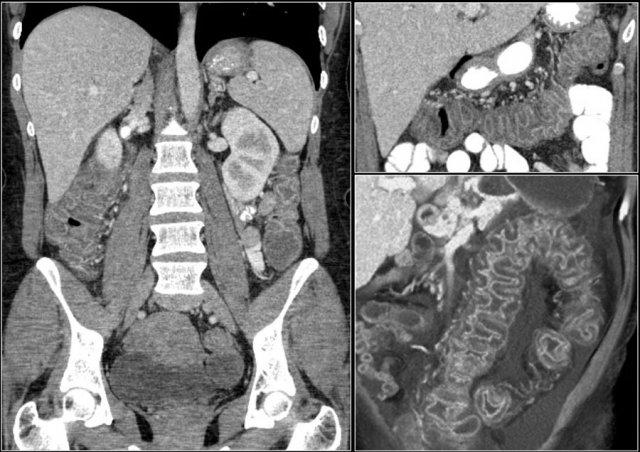

Tăng áp lực tĩnh mạch cửa

Tăng áp lực tĩnh mạch cửa là một nguyên nhân khác gây ra dấu hiệu bia nước.

Khi bệnh nhân bị tăng áp lực tĩnh mạch cửa, áp lực tăng cao sẽ được truyền đến đại tràng phải.

Điều này dẫn đến sự sản sinh các chất trung gian gây viêm và tăng sản xuất nitric oxide, gây tổn thương mô.

Hậu quả là xuất hiện viêm đại tràng khu trú ở bên phải.

Hãy phân tích các hình ảnh trước khi tiếp tục đọc.

Các dấu hiệu bao gồm:

- Xơ gan – bờ gan không đều

- Giãn tĩnh mạch và lách to

- Cổ trướng

- Viêm đại tràng bên phải

- Phình động mạch gan

Chẩn đoán phân biệt bao gồm:

- Tăng áp lực tĩnh mạch cửa

- Viêm đại tràng nhiễm khuẩn

- Viêm đại tràng thiếu máu cục bộ

Viêm đại tràng bên phải ở bệnh nhân xơ gan và tăng áp lực tĩnh mạch cửa. Hình ảnh nội soi là của bệnh nhân khác có viêm đại tràng bên phải.